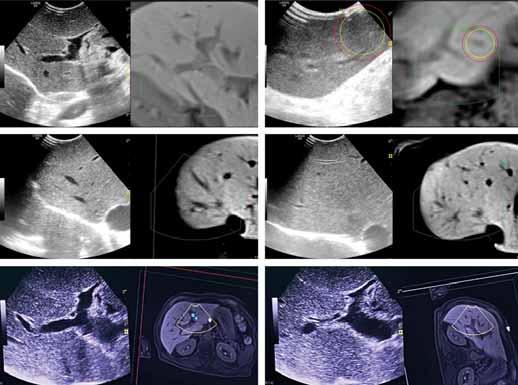

8.1. UNRESECTABLE COLORECTAL LIVER METASTASES